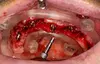

Fig 15 : sites d’extraction avec décollement de la gencive.

Étape 10 : extraction de la 13 plus difficile, avec décollement plus important de la gencive, GAM toujours en place.

Fig 16 : curetage alvéolaire.

Étape 12 : décollement un peu plus important, GAM toujours en place.